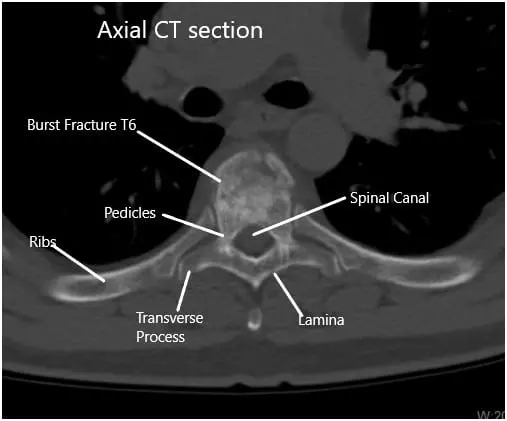

CT revealed moderate acute wedge compression fracture associated with the T6 vertebral body. The posterior cortex of the T6 vertebral body mildly impresses upon the anterior margin of the thoracic dural sac. Minimal hematoma is situated between the T6 vertebral body and the surrounding pleura.

There was a normal configuration of the remaining thoracic vertebral bodies. The thoracic disc spaces are not narrowed. Posterior disc bulges or herniations are not demonstrated. The narrowing is not associated with the thoracic neural foramina.

Preoperative CT Scan of the Thoracolumbar Spine in Axial Section at T6